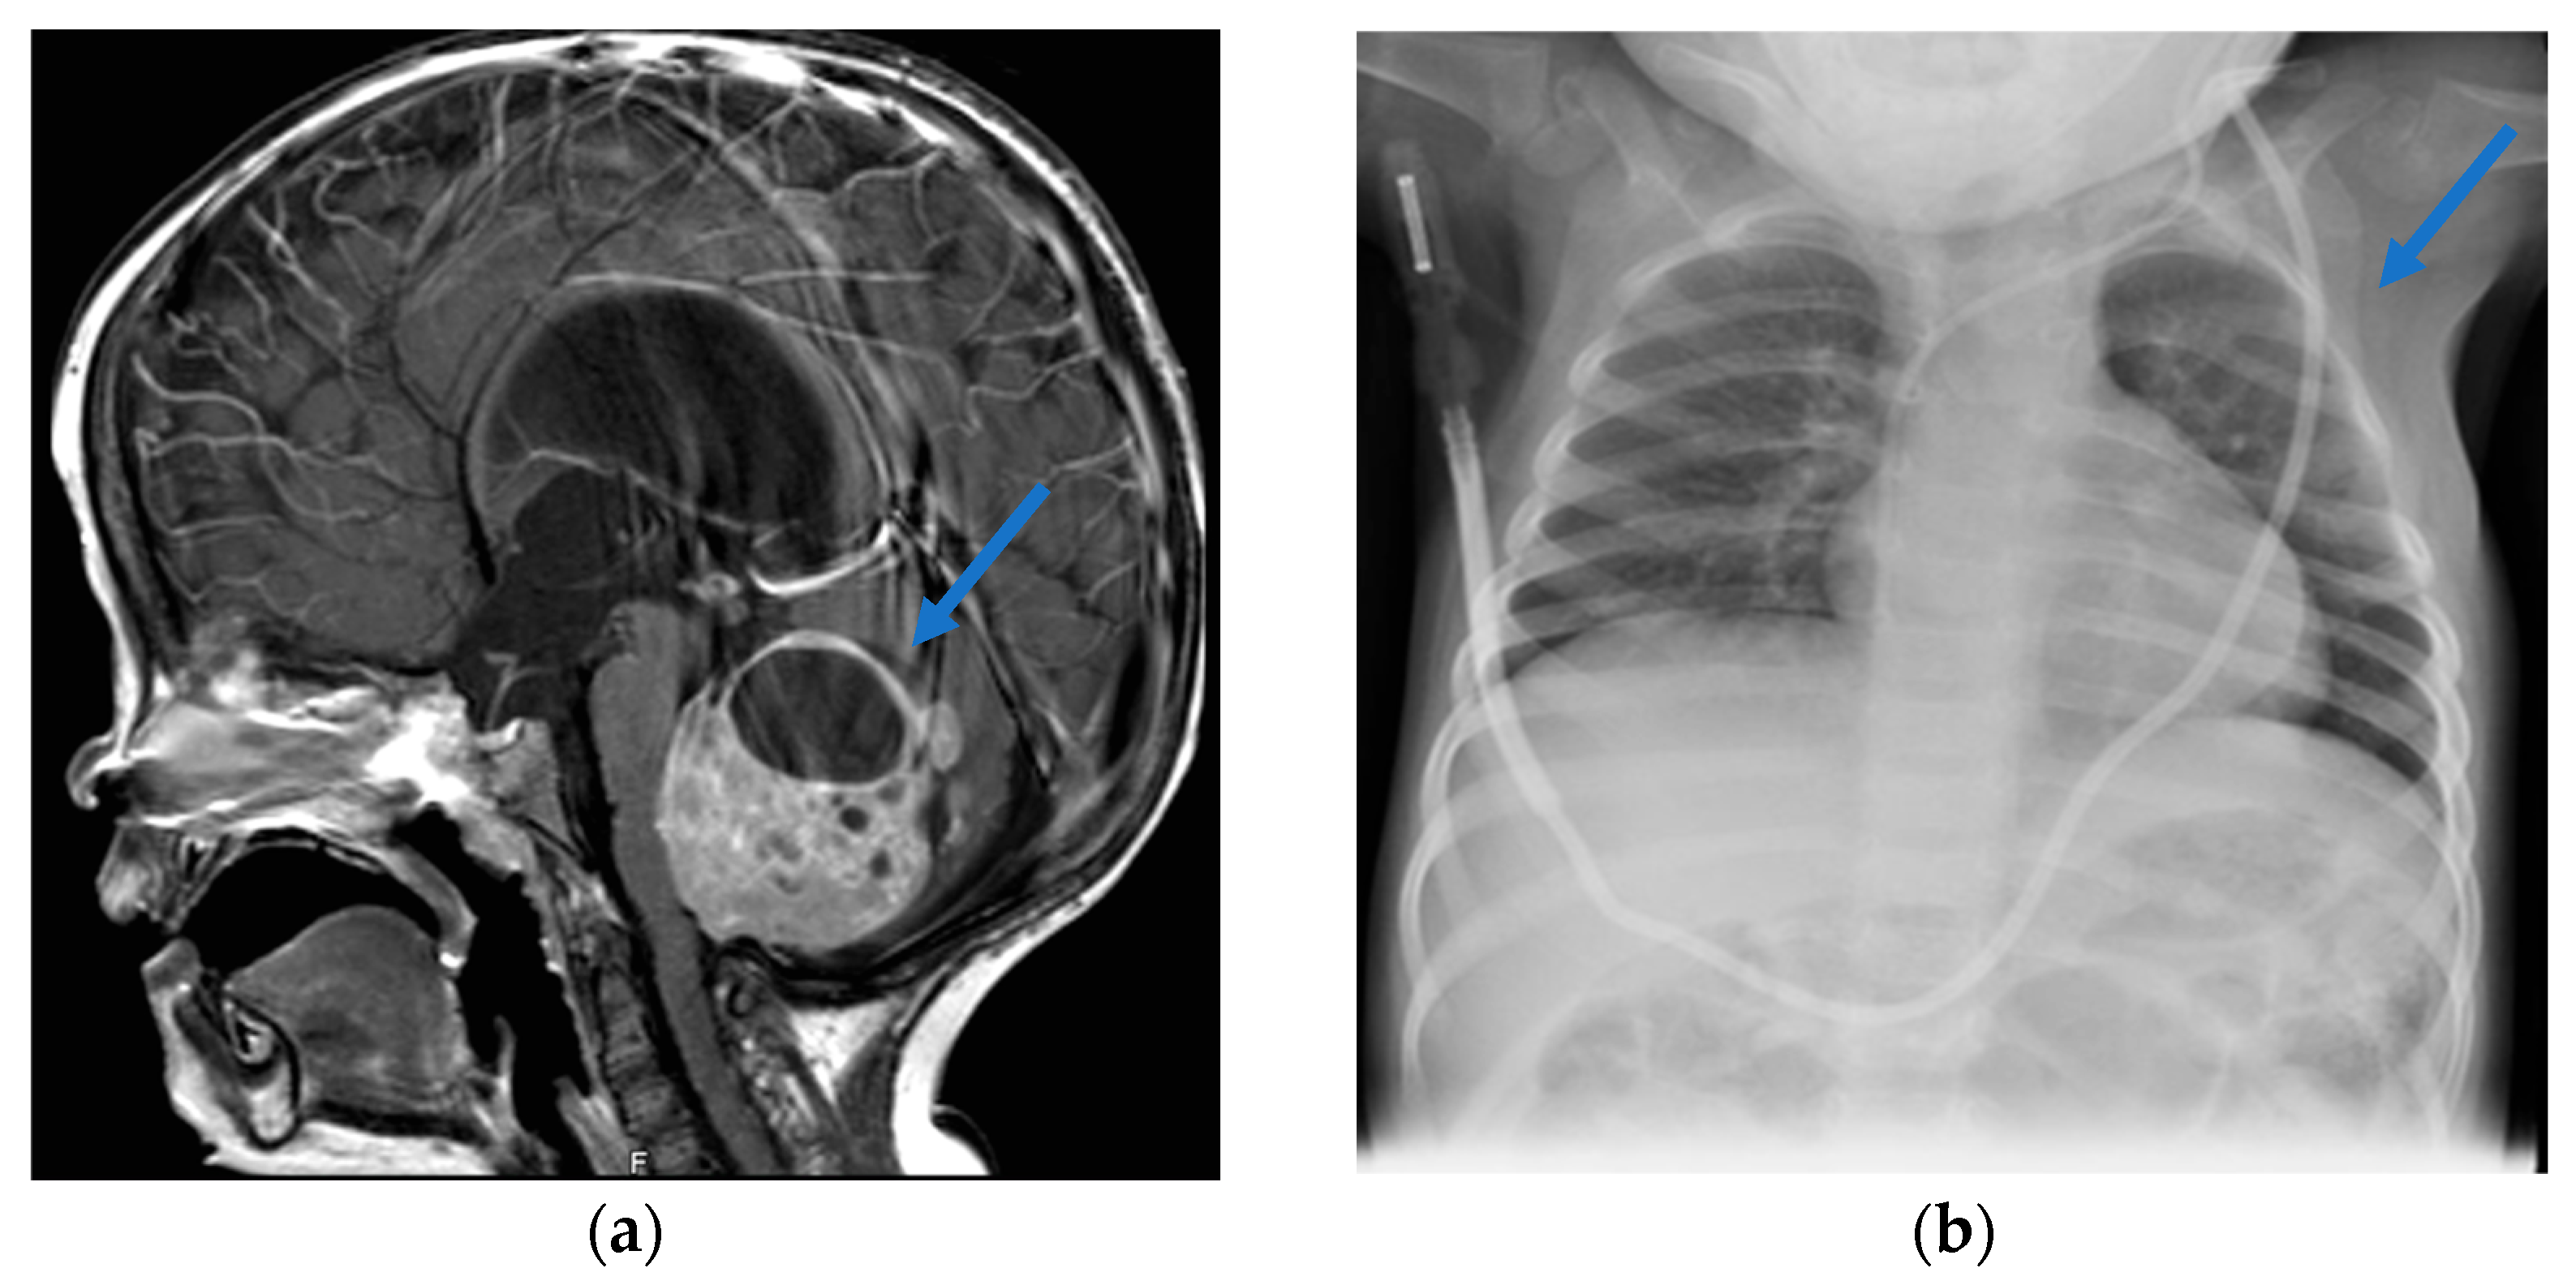

2. Case Report